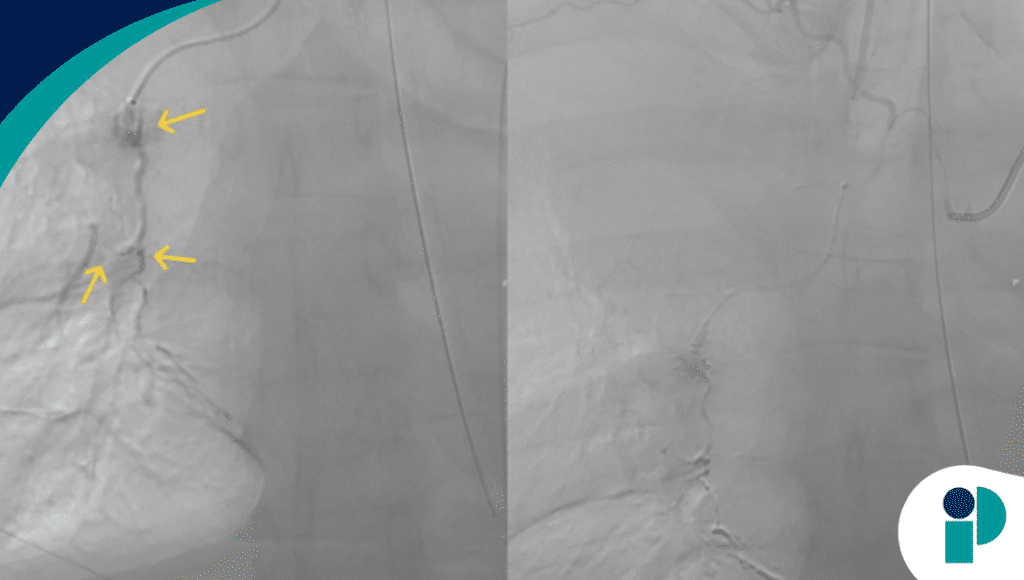

Una tomografía computarizada con contraste reveló un extenso hematoma en el mediastino superior derecho, acompañado de extravasación activa de contraste, lo que indicaba una hemorragia en curso. Inicialmente, la radiología intervencionista logró controlar el sangrado mediante embolización del vaso afectado. Sin embargo, la hemoptisis persistente y la inestabilidad del paciente obligaron a realizar una nueva embolización, esta vez en la arteria bronquial derecha, así como una broncoscopia diagnóstica.